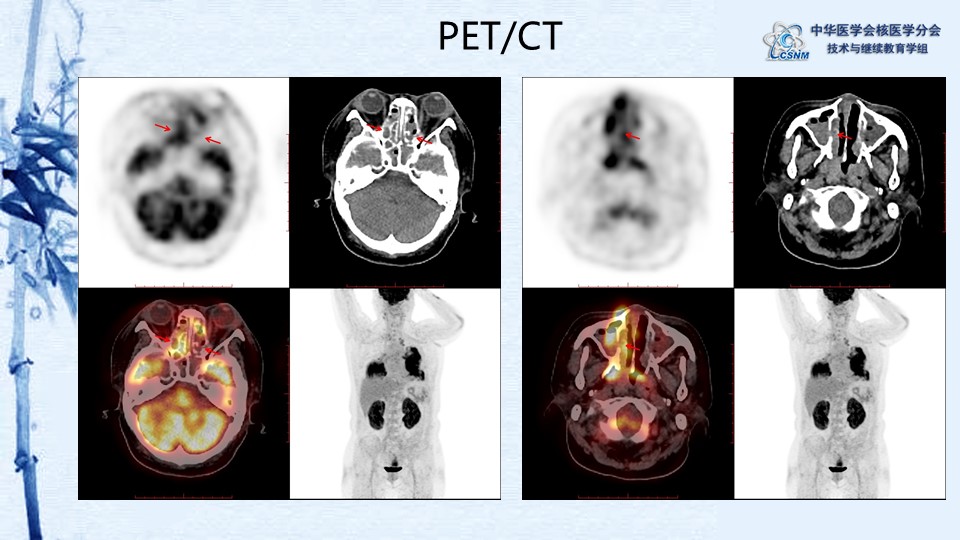

病例82:肉芽肿性血管炎PET-CT显像一例-【CSNM继教学组】郑山 福建医科大学附属第一医院